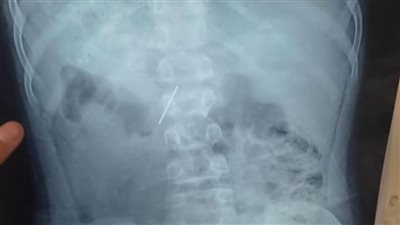

الأطفال التخصصي ينجح في استخراج "مسمار دباسة" اخترق جدار بطن طفل بالقليوبية